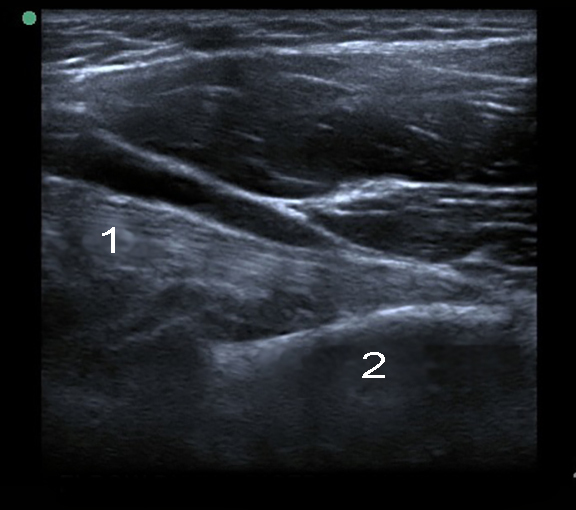

Elbow Distal Biceps Longitudinal

1. Biceps Tendon (BT)

2. Radial Tuberosity